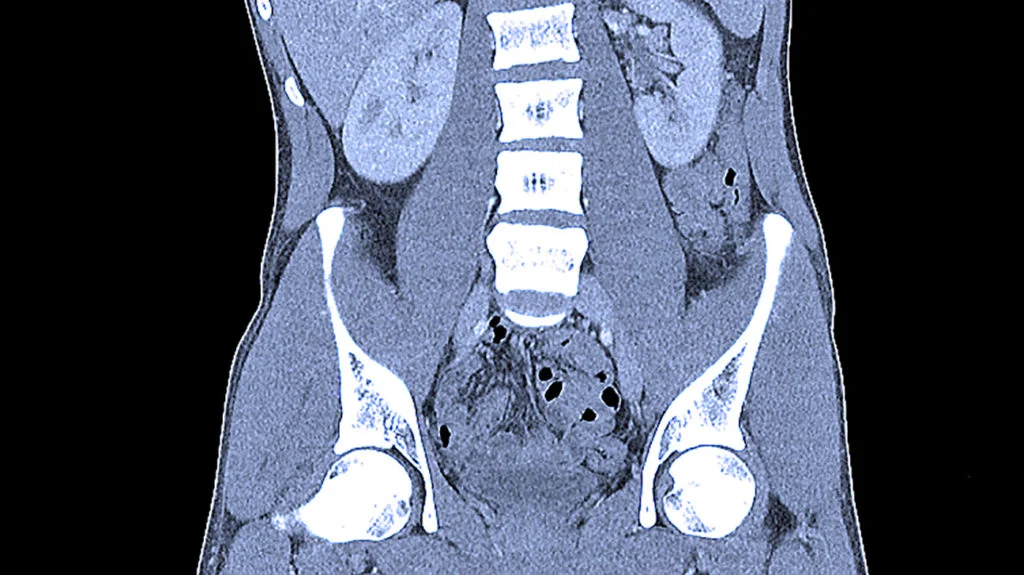

Комп’ютерна томографія (КТ) органів черевної порожнини, заочеревинного простору та тазу — неінвазивний метод діагностики, який дозволяє отримати детальні тривимірні зображення внутрішніх органів. Метод базується на використанні рентгенівського випромінювання та забезпечує візуалізацію органів, даючи змогу виявити патологічні зміни, оцінити структуру тканин, діагностувати запальні, пухлинні або травматичні ураження.

КТ органів черевної порожнини дозволяє детально оцінити стан паренхіматозних і порожнистих органів, судин і лімфатичних вузлів, а також виявити патологічні зміни та визначити їх локалізацію і поширення.

Комп’ютерна томографія дозволяє виявити об’ємні утворення (доброякісні та злоякісні), визначити їх розміри, межі та ступінь поширення, оцінити вплив на сусідні органи й тканини. На КТ-знімках пухлини органів черевної порожнини можуть візуалізуватися як ділянки зі зміненою щільністю, з чіткими або нерівними контурами, іноді з ознаками поширення в прилеглі тканини чи порушенням їхньої анатомії, що дає змогу лікарю оцінити характер процесу та запідозрити його природу.

Норма КТ органів черевної порожнини та таза у жінок і чоловіків визначається індивідуальними анатомічними особливостями та віком, тому показники можуть відрізнятися. У нормі на КТ відсутні ознаки запальних змін, новоутворень, кіст, абсцесів або крововиливів, а структура печінки, нирок, підшлункової залози та селезінки є однорідною. Органи мають правильне розташування, чіткі контури, судини — без ознак порушення кровотоку, а жовчні та сечовивідні шляхи — без розширення чи конкрементів (каменів).